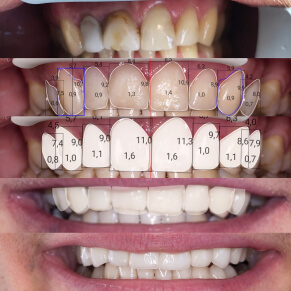

Komputerowe projektowanie uśmiechu

Co powinnaś wiedzieć o smile design?

Stomatologia estetyczna to dziedzina zajmująca się poprawą wyglądu zębów i estetyki uśmiechu. Jeśli chcesz odmienić swój uśmiech i skorygować niedoskonałości, skontaktuj się z nami! Przygotowaliśmy specjalny protokół, który pomoże nam zaplanować leczenie. Dotyczy on także większych prac protetycznych

Konsultacja SMILE DESIGN (ok 1.5h) obejmuje:

- Dokładny wywiad z pacjentem, wysłuchanie jego oczekiwań oraz powodów niezadowolenia z wyglądu swoich zębów (np. przebarwienia, stłoczenia, przerwy między zębami, zęby zbyt małe lub duże, braki zębowe itd.)

- Badanie zębów i całej jamy ustnej.

- Oprócz rutynowego przeglądu stomatologicznego badamy estetykę i przebieg linii uśmiechu, kształt zębów, zgryz.

- Odniesienie estetyki zębów do wyglądu całej twarzy, postury pacjenta, karnacji oraz wieku (np. dłuższe zęby przednie eksponowane w uśmiechu odejmą Ci wiele lat, sprawią, że będziesz wyglądać młodziej).

- Wykonanie zdjęć (fotografii) twarzy oraz uśmiechu.

- Wyciski diagnostyczne zębów, które wraz ze zdjęciami przesyłamy do laboratorium protetycznego. Technik protetyk wykonuje na modelach tzw. WAX UP, czyli ręcznie wymodelowany z wosku wygląd Twoich nowych zębów. Posłuży on w późniejszym etapie jako matryca do wykonania tymczasowych uzupełnień.